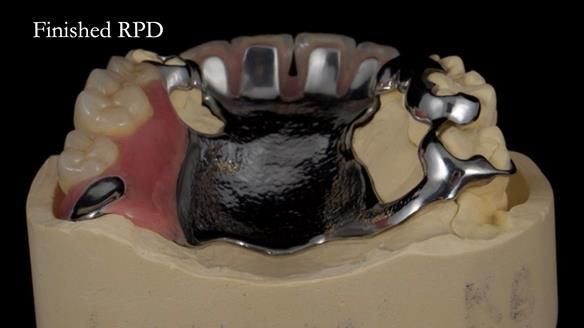

Keith’s case was one of the most challenging and rewarding cases I’ve treated this year. This 64 year old man presented with ill-fitting acrylic partial dentures that lacked stability, retention, and aesthetics. They constantly broke. He had lost the upper front teeth in a road traffic accident in his early 20s. The unopposed teeth had erupted, taking up space. After careful planning, we made a durable, metal-based upper partial denture/splint to address his dental concerns. He loved the outcome.

1. Denture design: A custom cobalt-chromium framework was Scandinavian-designed to maximise stability, protect the remaining teeth, and allow for future additions if needed.

Keith’s denture incorporated a Duracetal shell clasp on upper right first premolar (Myerson), which are designed to be virtually visible, providing a more aesthetic solution while enhancing patient comfort. The Scandinavian-inspired approach, based in modern removable prosthodontic techniques, ensured the denture was not only durable but also visually pleasing. Additionally, the design was carefully planned to allow for future modifications, ensuring that if Keith loses additional teeth, the denture can be adapted rather than replaced entirely.